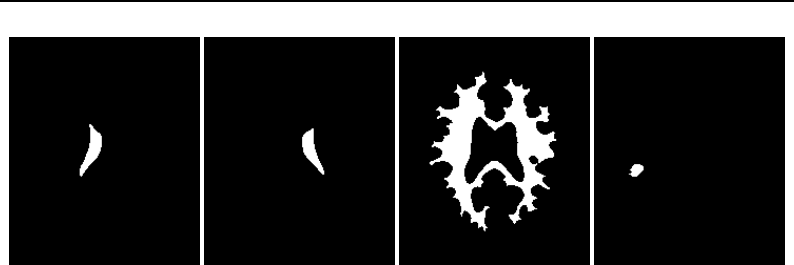

The Insight Toolkit (ITK) is an open-source, cross-platform system for medical image processing. It

provides medical imaging researchers with an extensive suite of leading-edge algorithms for

registering, segmenting, analyzing, and quantifying medical data. It is used in thousands of research

and commercial applications, from major labs to individual innovators.

The National Library of Medicine Insight Segmentation and Registration Toolkit, shortened as the

Insight Toolkit (ITK), is an open-source software toolkit for performing registration and segmenta-

tion. Segmentation is the process of identifying and classifying data found in a digitally sampled

representation. Typically the sampled representation is an image acquired from such medical instru-

mentation as CT or MRI scanners. Registration is the task of aligning or developing correspondences

between data. For example, in the medical environment, a CT scan may be aligned with a MRI scan

in order to combine the information contained in both.